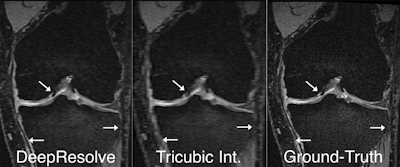

Two board-certified MSK radiologists then qualitatively ranked ground-truth images, DeepResolve images produced from images that had three times the thickness, and tricubic interpolation images. After reviewing the diagnostic quality of the three image sets for sharpness, contrast, artifacts, S/N ratio, and overall diagnostic quality, the radiologists preferred the DeepResolve images to those generated by the tricubic interpolation method commonly used in PACS and DICOM viewers, Chaudhari said. DeepResolve had significantly higher scores (p < 0.01) than the tricubic interpolation images in all image quality categories as well as overall image ranking.

Chaudhari and colleagues also concluded that DeepResolve did not seem to affect the visualization of pathology.